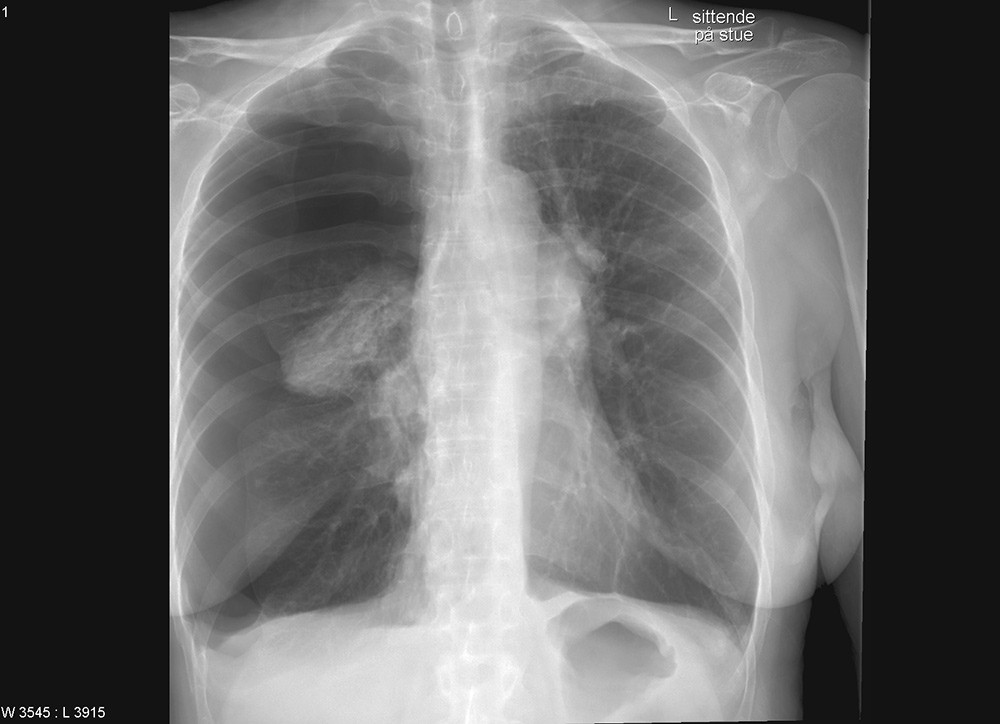

En kvinne i 60-årene var innlagt med svelgevansker og ernæringsproblemer. Hun var fra tidligere diagnostisert med supraglottisk plateepitelcancer og behandlet med utvidet strålefelt mot halsen og med cytostatika. Ved denne innleggelsen fikk hun lagt ned en tynn nasogastrisk sonde. Sonden hadde ytre diameter 1,95 mm og en stålmandreng. Den lot seg tilsynelatende føre ned ukomplisert. Ved instillasjon av 10 ml luft hørtes ikke bobler som normalt over magesekken. Røntgen av nedre thorax og øvre abdomen viste at sonden hadde fulgt bronkialtreet langt ut i høyre lunge (bilde til venstre). Sonden ble fjernet, men kort tid etter fikk kvinnen store pusteproblemer og stansalarmen måtte aktiveres. Røntgen thorax viste en stor høyresidig pneumothorax (bilde til høyre). Den ble vellykket behandlet med kirurgisk anlagt pleuradren.